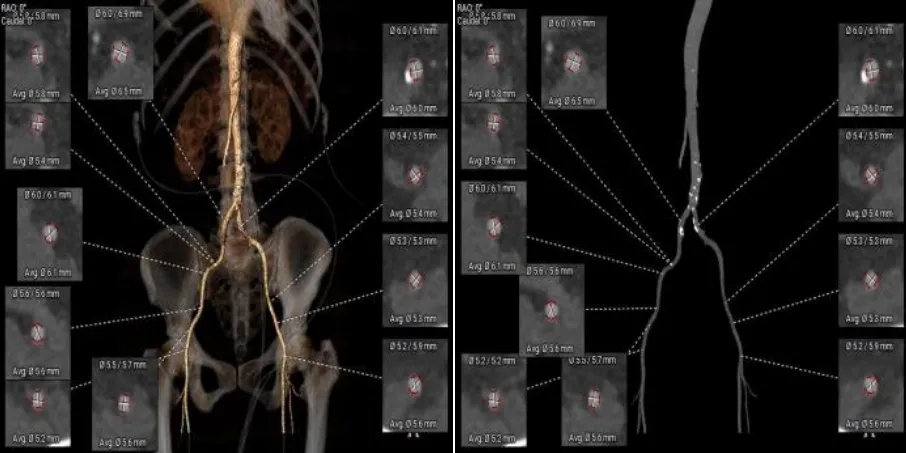

综合病例解剖特点及患者年纪,决定使用第二代可回收的自膨瓣,可回收提高容错空间,为了降低冠脉阻挡风险,决定采用平衡收腰设计的TaurusElite 的瓣膜,先使用大鞘鞘芯进行预扩,然后上20F大鞘。